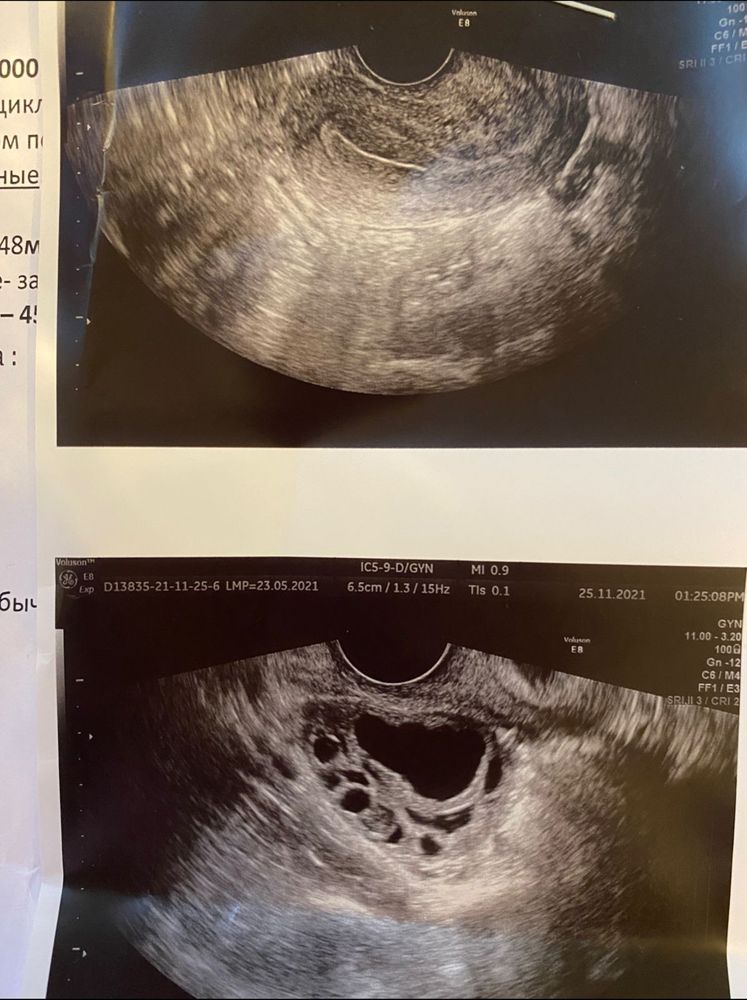

Виктория Север, в прошлом цикле (последняя фотка) и жидкость была, поэтому сказали что О. А сегодня ни жидкости, и сразу киста с кровоизлиянием написали. Я думала доминантный фолликул должен быть немного темнее

Вот это с прошлого